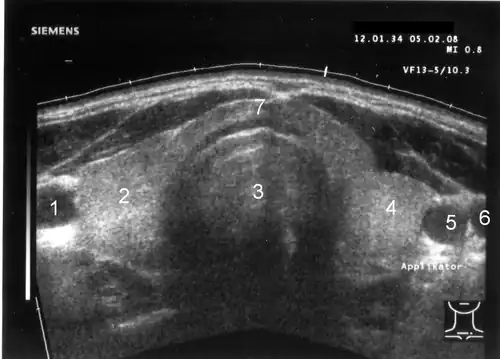

1 Arteria carotis communis rechts, 2 rechter Schilddrüsenlappen, 3 Trachea, 4 linker Schilddrüsenlappen, 5 Arteria carotis communis links, 6 Vena jugularis interna links, 7 Isthmus (Gewebebrücke zwischen rechtem und linkem Schilddrüsenlappen)

Sonografie

In der bildgebenden Diagnostik wird zunächst der Ultraschall eingesetzt. Es wird für die Schilddrüse der Einsatz von Realtime-Geräten empfohlen. Die Sendefrequenz des Schallkopfes sollte eine Mittenfrequenz 7,5 MHz nicht unterschreiten; eine bessere Detailauflösung insbesondere in oberflächennahen Strukturen bieten Schallköpfe mit einer höheren Sendefrequenz von bis zu 13,5 MHz. Neue Geräte bieten zum Teil höhere Sendefrequenzen bis 17 MHz (Stand 2010). Eine Bildbreite von etwa 6 cm erlaubt in der Mehrzahl der Fälle von vergrößerter Schilddrüse die Bestimmung des Gesamtdurchmessers; Linearschallköpfe mit größerer Bildbreite können die Untersuchung bei Patienten mit kurzem Hals erschweren.

Lateral der Schilddrüse sind die Arteria carotis communis (rund, pulsierend und kaum komprimierbar) und die Vena jugularis interna (sichelförmig, leicht komprimierbar) erkennbar. Links hinter der Schilddrüse lässt sich die Speiseröhre abgrenzen. Weitere Orientierungsstrukturen sind rechts und links der Musculus sternocleidomastoideus sowie die Vorderkante der Wirbelkörper der Halswirbelsäule.